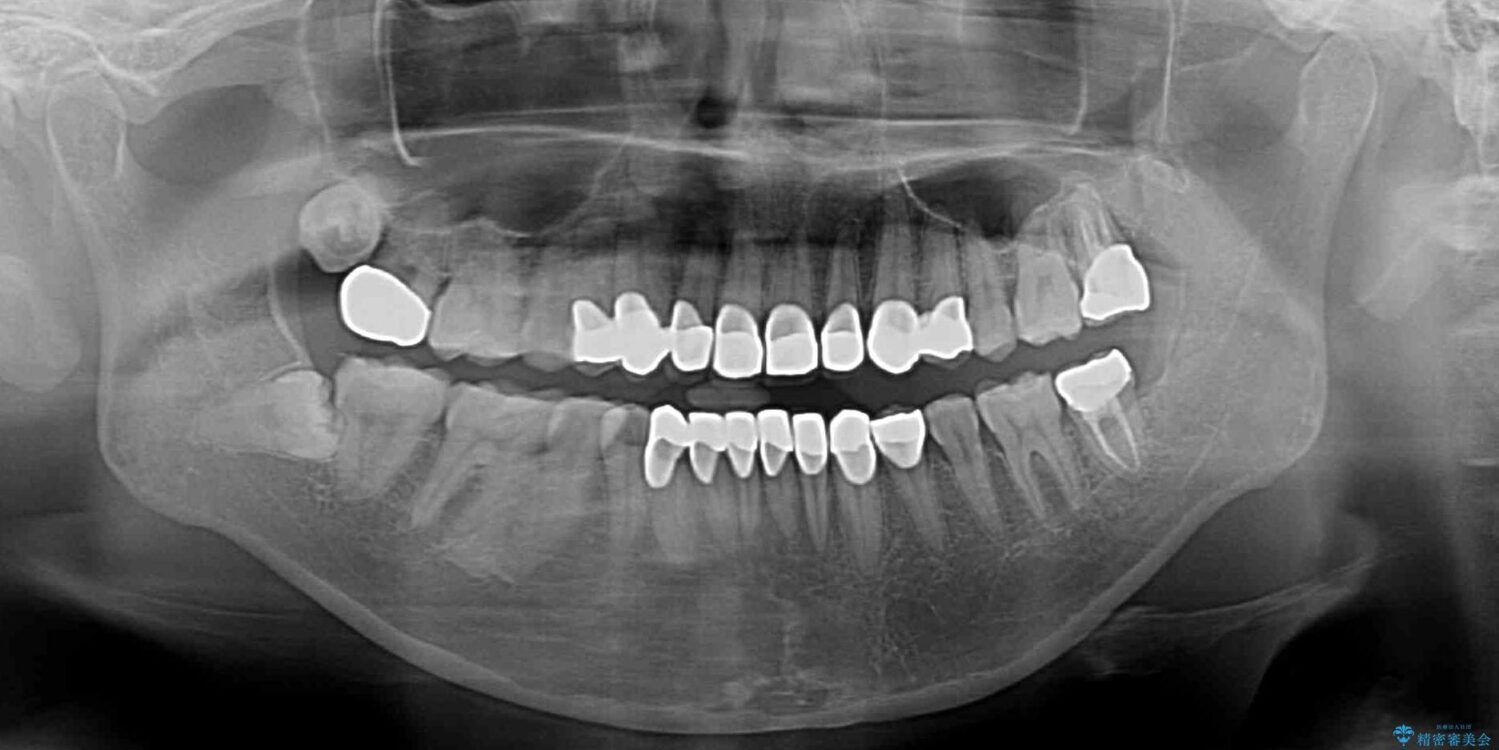

全顎的にむし歯が多く、根管治療の必要な奥歯や、審美的に気になっている前歯を中心にオールセラミッククラウンにて補綴治療を行うこととしました。

上顎前歯は歯肉退縮により歯根が露出していたため、事前に歯肉移植術により根面被覆を行い、その後にオールセラミッククラウンを装着することとしました。

治療前

• むし歯だらけの前歯をオールセラミッククラウンできれいに 治療前画像